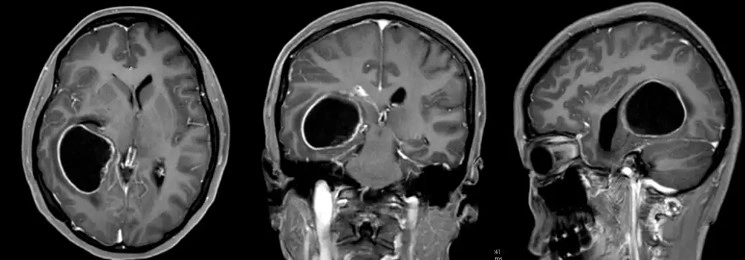

Pre-surgical scan results of patient Lam. Photo: Ycwb |

Doctor Dang Thieu Dung received Lam, who was experiencing continuous vomiting and semi-consciousness. MRI results confirmed the tumor was causing hydrocephalus. The neurosurgery department VII team immediately consulted and decided to surgically remove the tumor. Department head Ngo Thai Hoa directly and completely resected the tumor along the lesion's border, while preserving the integrity of the lateral ventricular structure. Throughout the surgery, doctors used a neurophysiological monitoring system to ensure the highest precision.

Post-operative histopathological analysis concluded that Lam had a high-grade diffuse glioma (grade 3-4 according to the World Health Organization - WHO classification), indicating a very high malignancy. Ten days after the surgery, the patient recovered, walked normally, and was discharged without sequelae. She admitted to previously ignoring persistent headaches and dizziness. The mother vowed to stop pushing her child to study to the point of exhaustion.